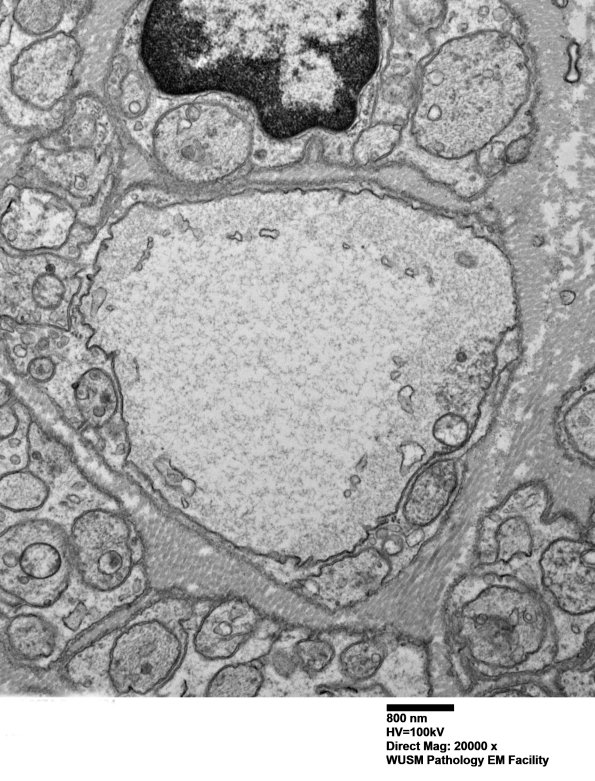

Higher magnification of pale pre-myelinated axons. (electron micrograph)